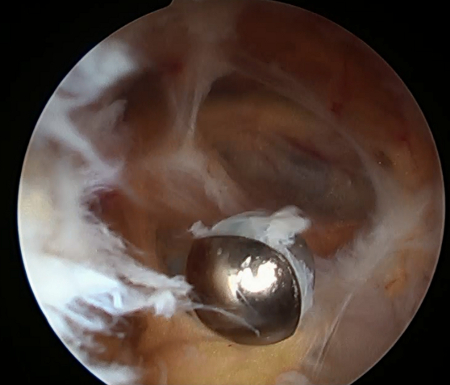

Patologias do joelho, como trauma, artrite ou infecção, podem resultar no aumento de volume e da pressão do líquido sinovial.[17][18] Derrames se desenvolvem quando a absorção do líquido sinovial sofre um atraso em relação à filtração microvascular. A pressão intra-articular aumenta significativamente durante a extensão do joelho e isso pode explicar por que a dor frequentemente ocorre nessa posição. Embora muitos relatos tenham sugerido uma fraqueza inerente na cápsula posterior, nenhum dado apoia essa hipótese.[Figure caption and citation for the preceding image starts]: Sinovite dentro do cistoDo acervo do Dr John D. Kelly IV; usado com permissão [Citation ends].